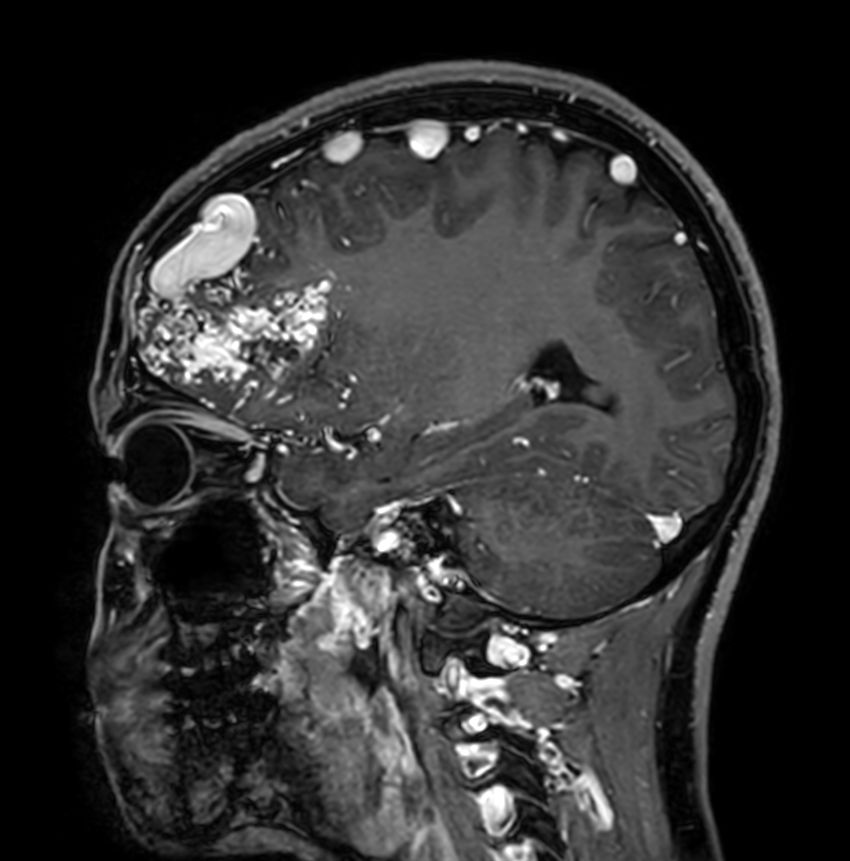

Sagittal 3D T1w TFE +gadoCompressed SENSE

Sagittal 4D-TRAK XD